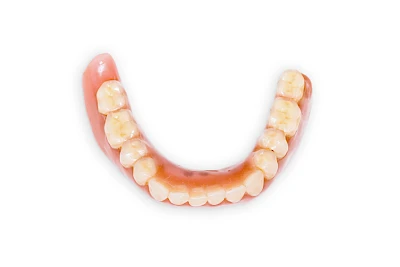

Implantate: Prothesen

Bei herausnehmbaren Prothesen werden Implantate eingesetzt, um den Halt und den Tragekomfort der Prothesen zu verbessern. Dazu kommen verschiedene Verbindungselemente zum Einsatz:

- Teleskope

- Kugelköpfe

- Tellerförmige Lokatoren

- Stege

- Magnete (selten)

Neben rein implantat-getragenen zahnärztlichen Versorgungen werden bei herausnehmbaren Prothesen Implantate auch in Sinne einer "strategischen Pfeilervermehrung" ergänzend zu eigenen Zähnen zur Verankerung eines Zahnersatzes genutzt.

Varianten zur Verankerung von abnehmbarem Zahnersatz auf Implantaten